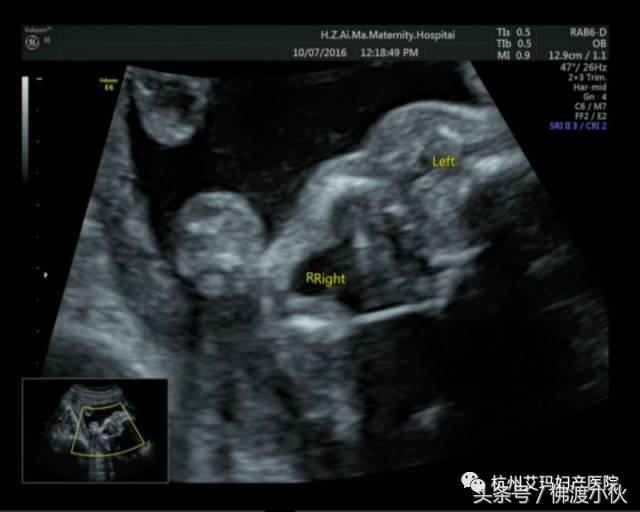

病例一:

胎儿左眼未见明显眼球结构,右眼未见晶状体回声,考虑左眼小眼球、右眼晶状体缺失(见下图)。